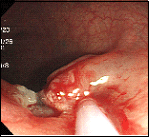

79歳の女性。心窩部痛・黒色便の訴えで受診しました。胃の中は血液で充満し、胃角部(胃の中央部)に大きな深掘れ型の潰瘍を認め、血管が剥き出しになりチョロチョロと出血していました。クリップを用いて血管を潰し、止血しました。